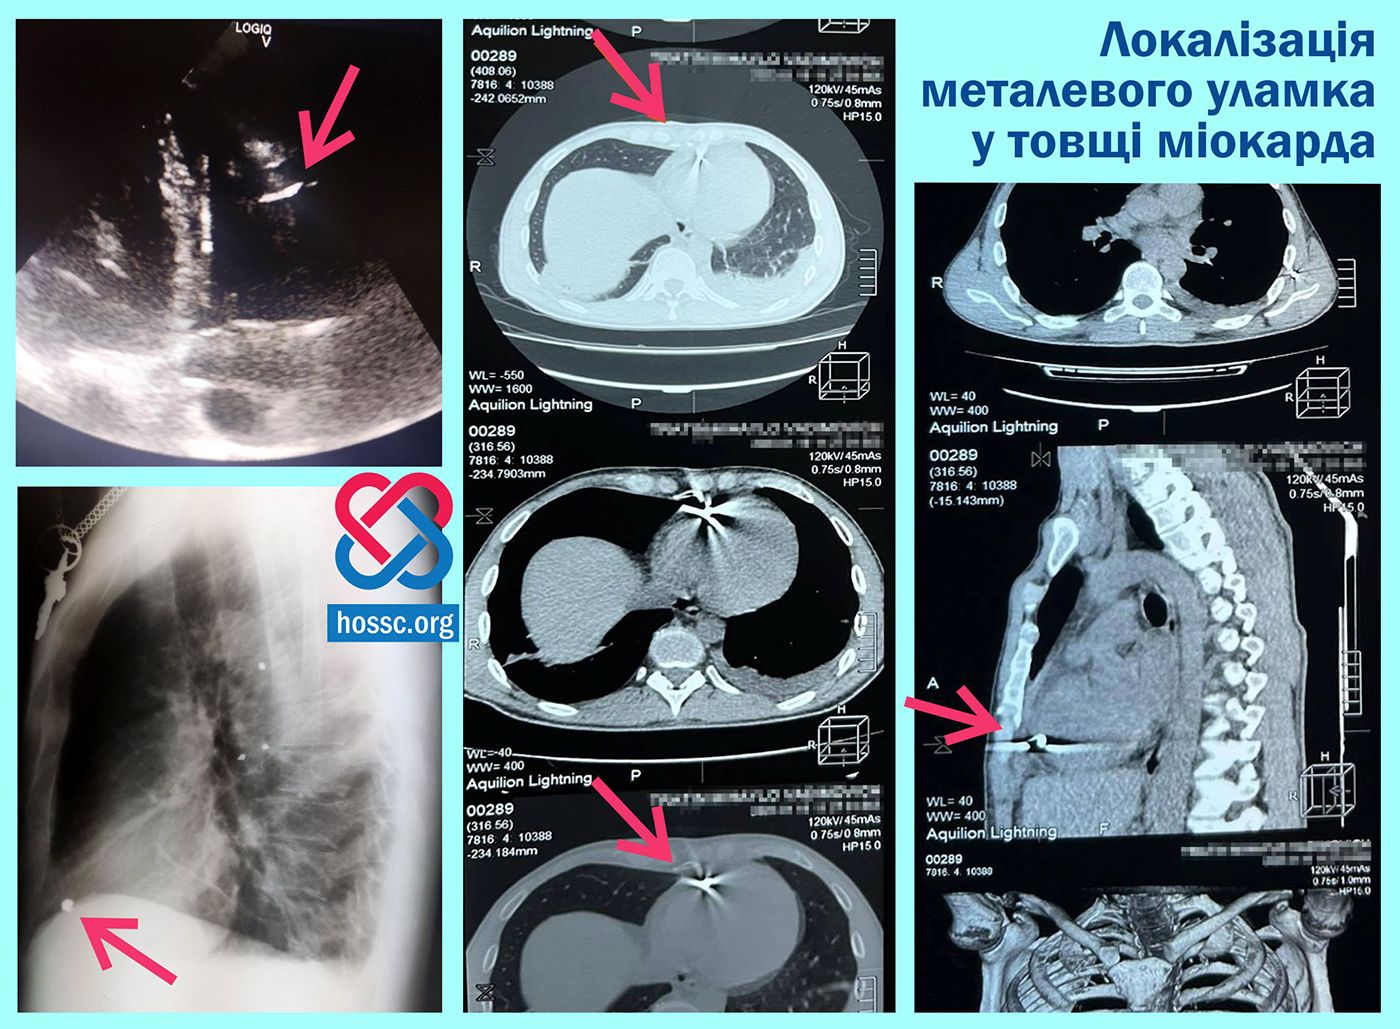

Хмельницькі лікарі витягнули уламок міни із серця військового (ФОТО)

Уламок, діаметром 1 сантиметр, застряг у правому шлуночку.

Захисник України— 40-річний тернопільчанин — у боях на Дніпропетровщині отримав мінно-вибухові поранення. Медики знайшли у його тілі металевий уламок діаметром більше 1 сантиметра. Він знаходився в ділянці серця.

Хмельницькі лікарі провели обстеження, ехокардіоскопію та комп’ютерну томографію і встановили точну локацію уламку – у товщі міокарда правого шлуночка.

Після цього провели складну операцію на відкритому серці, яке продовжувало битися під час втручання. Медикам вдалося успішно видалити металевий уламок з серцевого м’яза та зробити реконструктивне втручання.